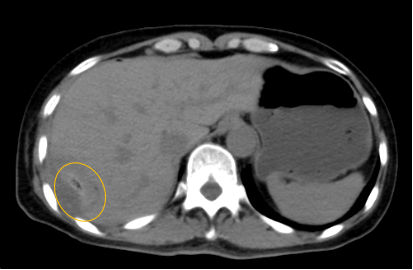

入院后,影像診療中心立即給李女士完善了CT和MR檢查,發(fā)現(xiàn)病變位于肝包膜下,臨近膈肌,消融治療過程中有并發(fā)損傷膈肌的可能,難度較大,但是采用精準(zhǔn)影像定位是可以完成的。陳寶瑩主任立即與腫瘤三病區(qū)劉金鵬主任聯(lián)系,并與影像微創(chuàng)治療小組進行MDT討論:患者為卵巢癌肝右葉包膜下單發(fā)轉(zhuǎn)移瘤,最長徑不超過3cm,患者對局部治療的主觀愿望強烈,符合消融治療專家共識,遂制定了影像引導(dǎo)下局部消融治療聯(lián)合全身治療的綜合治療方案。

針對這個特殊部位的腫瘤,要想消融完全,那么膈肌損傷的風(fēng)險就很高,陳寶瑩主任帶領(lǐng)影像微創(chuàng)亞專業(yè)組成員仔細(xì)閱讀CT圖像,設(shè)計進針路徑,結(jié)合MR圖像確定腫瘤活性范圍,制定了周密而詳盡的消融計劃。臘月二十九,即住院第二天影像微創(chuàng)治療小組圓滿為患者完成了腫瘤微波消融治療,觀察24小時后出院回家過年。術(shù)后48小時隨訪患者無明顯不適,術(shù)后7天隨訪,患者肝功、血常規(guī)等各項指標(biāo)均恢復(fù)正常。